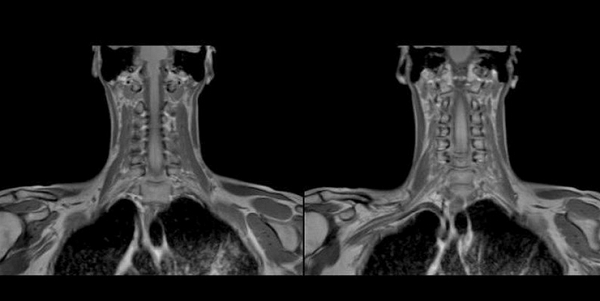

Снимки МРТ мягких тканей шеи

Магнитно-резонансная томография обеспечивает детальную визуализацию рыхлых структур. В результате сканирования получают послойные изображения щитовидной железы, расположенных рядом лимфатических узлов, кровеносных сосудов, мягких тканей шеи, гортани.

Исследование отличается высокой информативностью по сравнению с другими методами аппаратной диагностики. Томограммы показывают изменения формы и размеров анатомического образования, позволяют выявить структурные нарушения и патологические очаги диаметром от 3 мм.

При увеличении железы в размерах по описанию томограмм можно определить характер гиперплазии. Узелки и капсулы выглядят на снимках МРТ как очаги с гипо- или гиперинтенсивным сигналом, отличным от реакции окружающих тканей. Метод показывает сдавление трахеи новообразованием, распространение патологического процесса в загрудинное пространство.

Мягкие ткани шеи на МРТ

Благодаря резонансному движению заряженных частиц в ответ на воздействие магнитного поля метод визуализируют структурное перерождение тканей, изменение формы, размеров, контуров сканируемого органа. Послойные фотографии, сделанные в аксиальной, фронтальной и сагиттальной проекциях, отображают малейшие трансформации щитовидной железы, включая патологии кровеносных сосудов.

Метастазы на снимках МРТ шеи

Рисунок 1,2. МРТ мягких тканей шеи (Т2-ВИ и Т1-fs-ВИ контрастное усиление). Патологических образований в структуры щитовидной железы не выявлено.